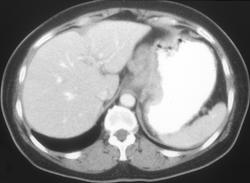

Gastric Cancer